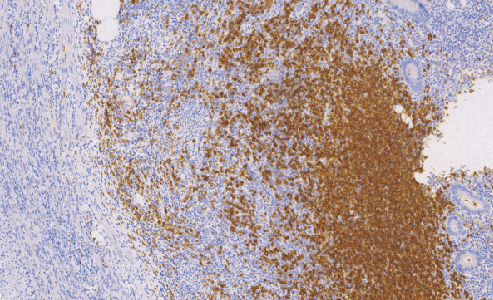

CD20鼠抗人CD20单克隆抗体

CD20抗原是一种非糖基化磷蛋白,分子量大约为33KD,表达在人的正常B细胞和恶性肿瘤B细胞中,并被认为在B细胞活化和分化中起受体的作用。据文献报道CD20抗原在外周血正常的B细胞中,淋巴结、脾脏、扁桃体、骨髓,急性白血病和慢性淋巴细胞白血病中都有表达。

- 阳性部位:胞膜

- 适用组织:石蜡切片

- 预处理:热修复